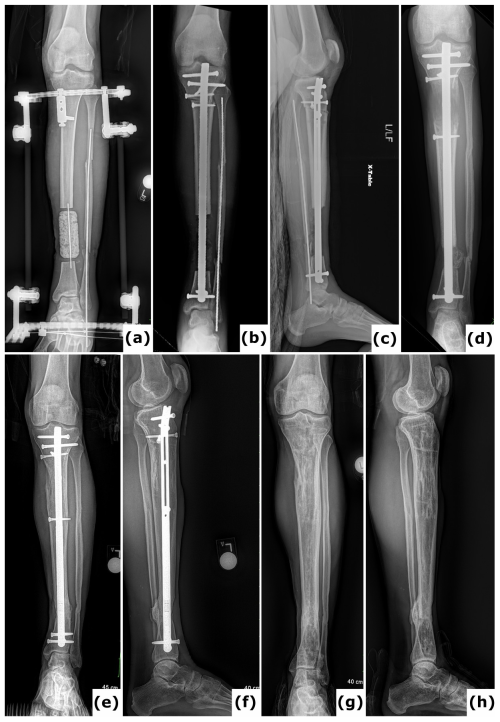

Figure 2Fracture-related infection (FRI) of the tibia. An 18-year-old patient presented with a Gustilo-Anderson type III open fracture of the tibia and fibula. (a) Anteroposterior radiograph demonstrates a comminuted fracture of both the tibia and the fibula. (b) The anteroposterior radiograph indicates fixation of the fracture using an intramedullary nail. The defect was managed with MIMT. (c) Six months post-injury, the patient was referred with multiple fistulas, confirming FRI. (d–e) Anteroposterior radiograph and computed tomography (CT) images were taken after the revision procedure. Removal of the implant and thorough surgical debridement resulted in a large segmental bone defect. The images show the progression of bone transport over a 10 mm intramedullary nail. White arrows point to the off-label locking hole created during the procedure. Once bone transport is complete, the segment can be secured with a 4 mm interlocking screw and the frame can be removed, which reduces the external fixation time.

Figure 3Bone transport utilizing external fixation. A 51-year-old patient presented with a Gustilo-Anderson type II open fracture of the distal tibia and fibula. (a) Clinical presentation upon admission to the emergency department, illustrating the open fracture. (b–c) Computed tomography (CT) images obtained at the time of referral, 3 months after initial stabilization with a standard external fixator, reveal absence of bone healing and significant destruction of the tibiotalar joint. (d–e) Anteroposterior radiographs demonstrate ongoing bone transport using a conventional ring fixator. Intraoperative cultures were negative. Note: Due to severe peripheral artery disease, there was a high risk of amputation; consequently, the corticotomy was performed at a lower level than the standard metaphyseal site. (f–i) CT scans, as well as anteroposterior and lateral radiographs, confirm complete consolidation at all sites at 2 years post-procedure. (j) Clinical evaluation at 2 years showed no signs of infection, and the patient was able to ambulate independently.